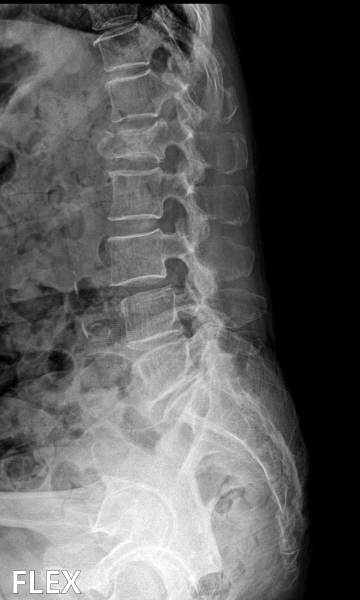

척추 고정술 치료 방법

2020.06.09

2020.08.11

ㆍ환자 동의를 받은 자료이며, 이미지 사진은 실물과 다를 수 있습니다.

ㆍ모든 자료는 새움병원 자료입니다.